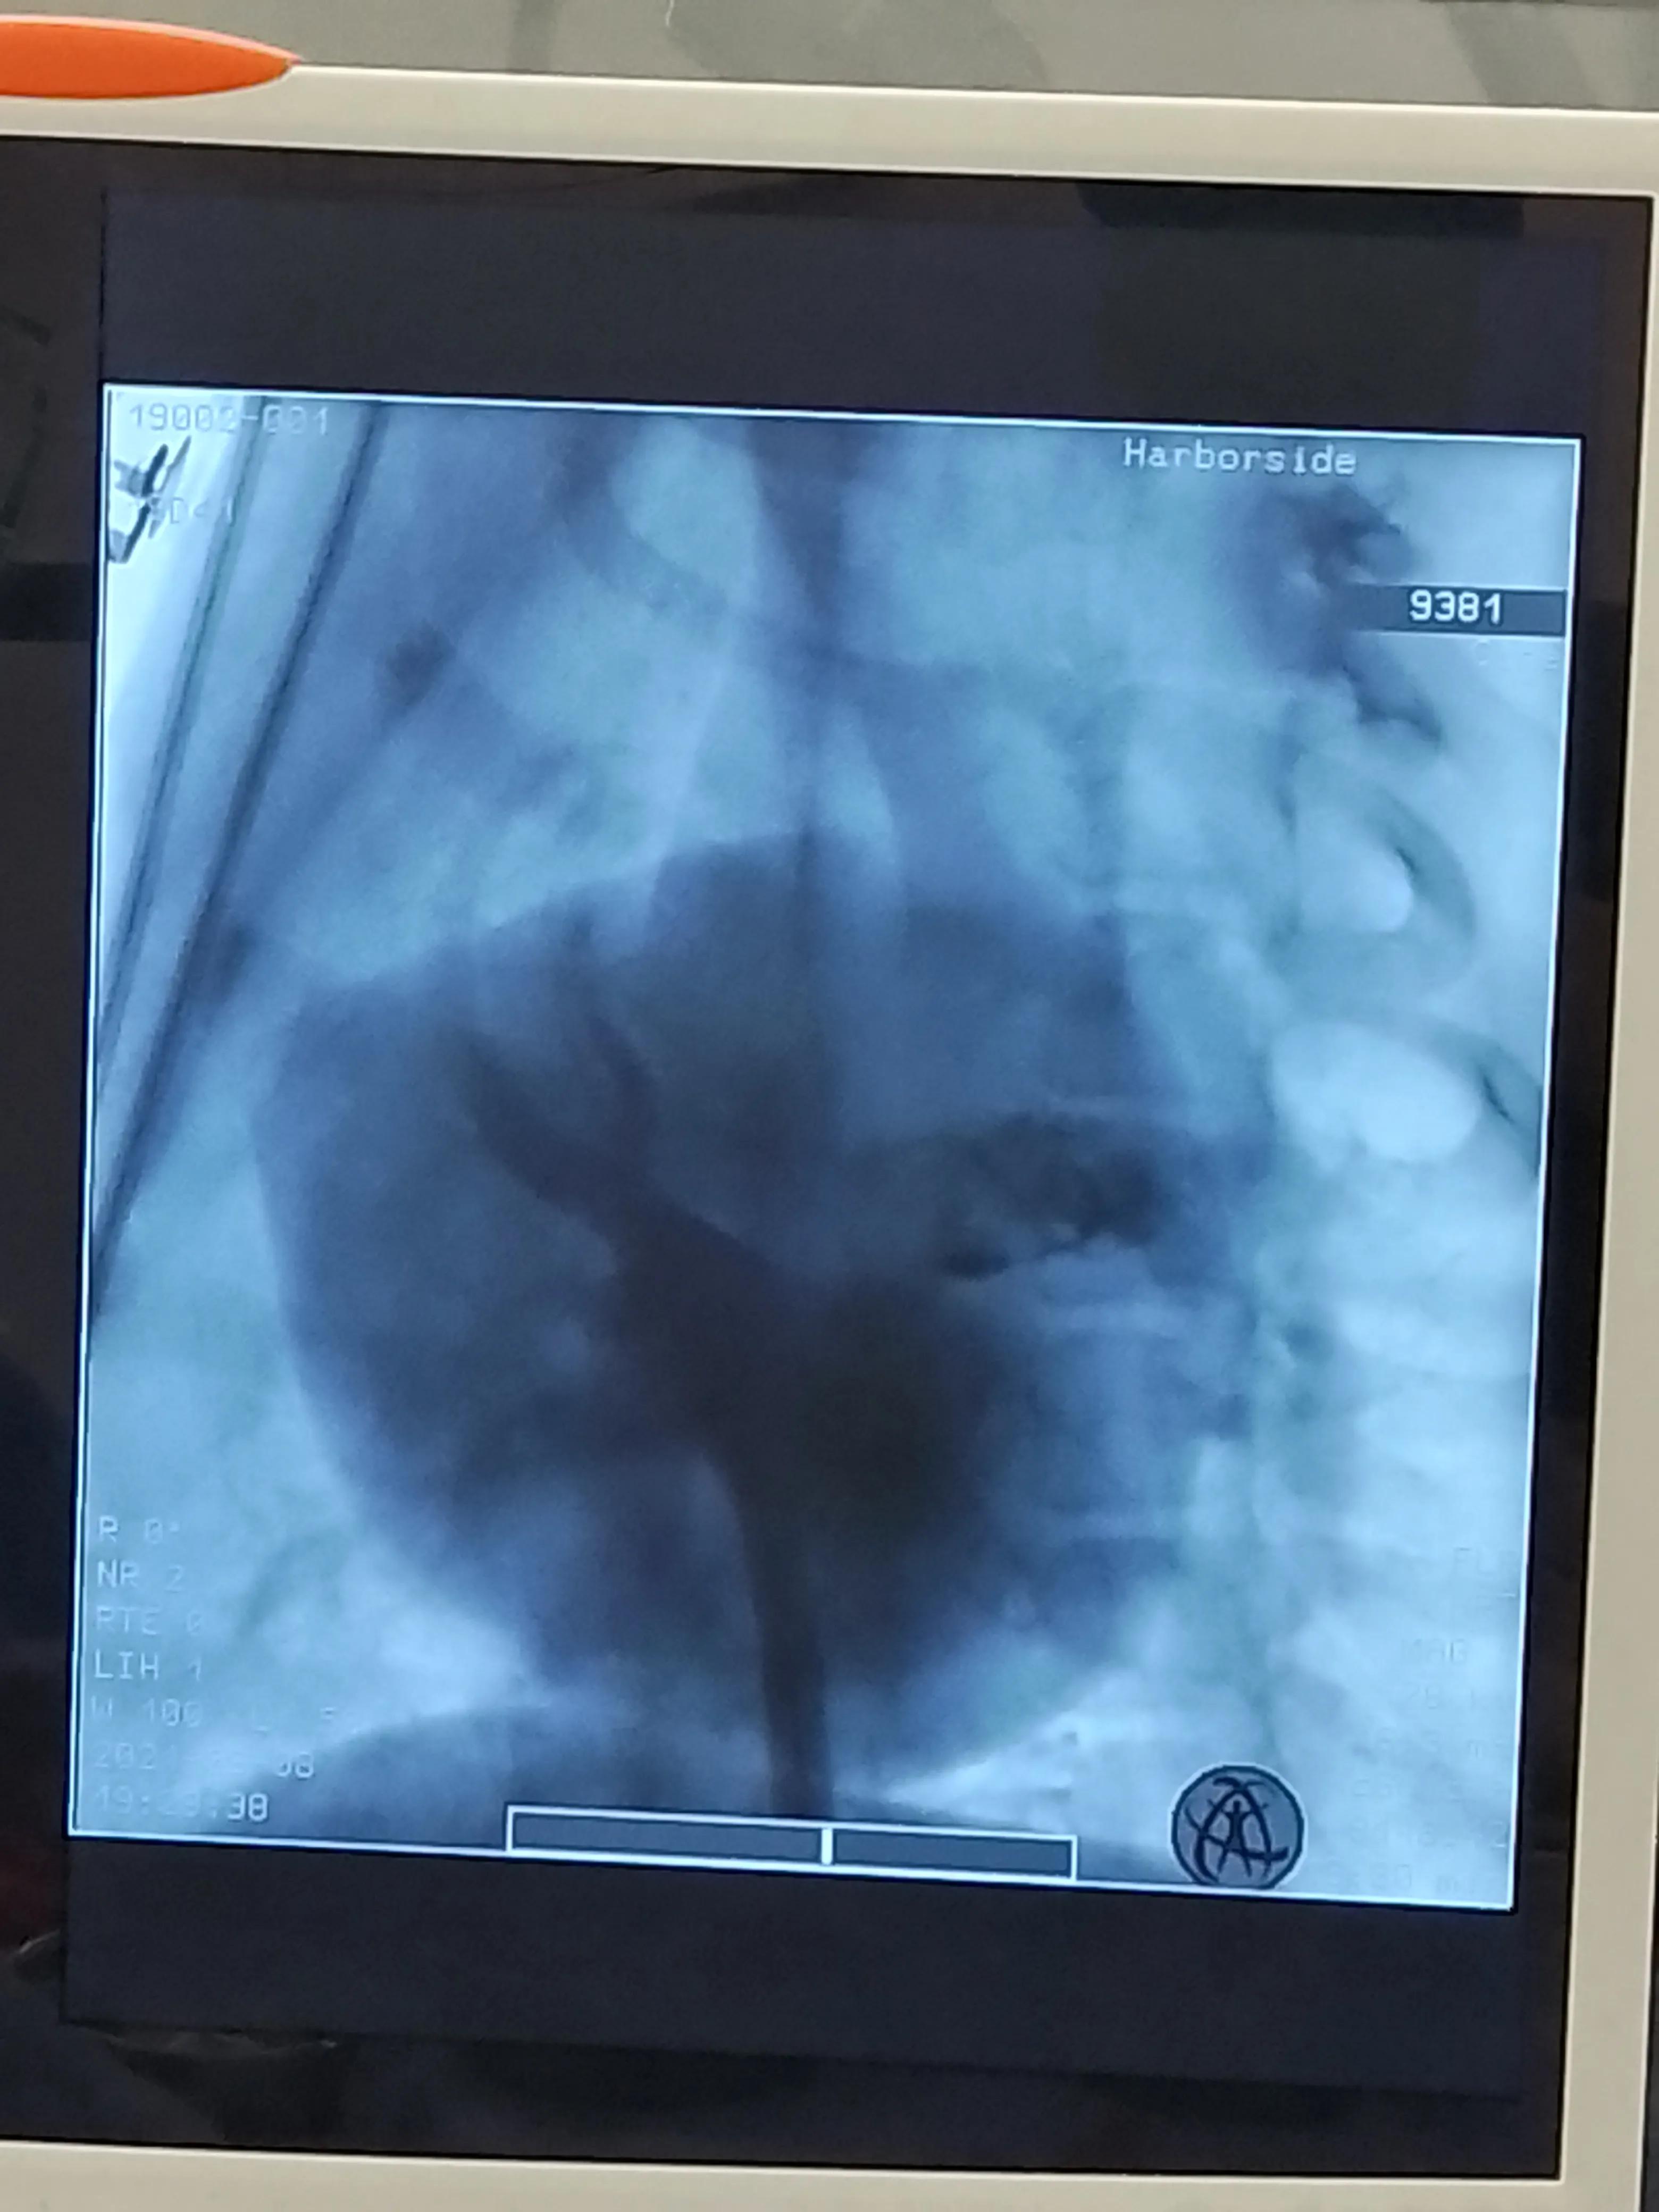

右肺静脉显影